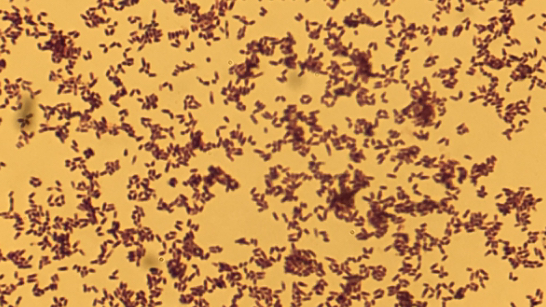

Discussion: Most patients with disseminated Cryptococcus infection are immunocompromised. It can take several weeks for fungal smear and culture results to be finalized, and delay in treatment approach can be avoided by keeping high clinical suspicion for disseminated cryptococcal infection. Gordonia species are gram positive, weakly acid-fast aerobic coccobacilli and belong to the actinomycetes family. It rarely causes infections in humans. Microbiologic diagnosis of Gordonia species is challenging, often leading to incorrect identification as Rhodococcus or Nocardia, as occurred in this case.